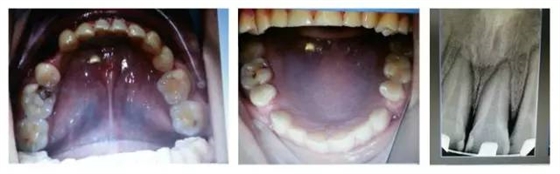

口內(nèi)情況,如以下照片所示:

您是否首先會想到,患者的牙齒是受外力撞擊引起的牙周膜急性創(chuàng)傷?或是(牙合)創(chuàng)傷引起?如果是創(chuàng)傷,這種創(chuàng)傷是如何形成的呢?權(quán)老師提示一,患者并無外傷史,進(jìn)食很小心;提示二,從口內(nèi)照片可得知患者前牙無接觸,(牙合)創(chuàng)傷從何而來呢?

群里多位同仁已經(jīng)發(fā)現(xiàn)了它的不和諧之處,劉坦,劉曉強(qiáng)等多位醫(yī)生先后發(fā)現(xiàn):患者前伸(牙合)后牙有干擾。其他同仁也同時提出或需要進(jìn)行適當(dāng)?shù)恼{(diào)(牙合),或使用后牙(牙合)墊抬高后牙咬合,方能解決急性創(chuàng)傷。仔細(xì)看口內(nèi)的照片,從咬合的觀點(diǎn)和理論角度出發(fā),您捕捉到什么信息了嗎?

由上圖可知,患者全口牙齒磨耗較重,尖牙牙尖磨耗,無法起到引導(dǎo)和保護(hù)作用,上前牙牙根短,上中切牙腭側(cè)面邊緣嵴消失,

由此推斷:尖牙牙尖磨耗,患者在前伸(牙合)運(yùn)動時,引導(dǎo)不足,前牙的接觸面過大,受力較大;患者在側(cè)方(牙合)運(yùn)動時下前牙沒有了引導(dǎo),會直接對側(cè)切牙造成撞擊;再加上前牙根較短,無法耐受,引起(牙合)創(chuàng)傷,繼發(fā)牙髓癥狀;失去尖牙保護(hù)(牙合),加重了牙齒的磨耗。